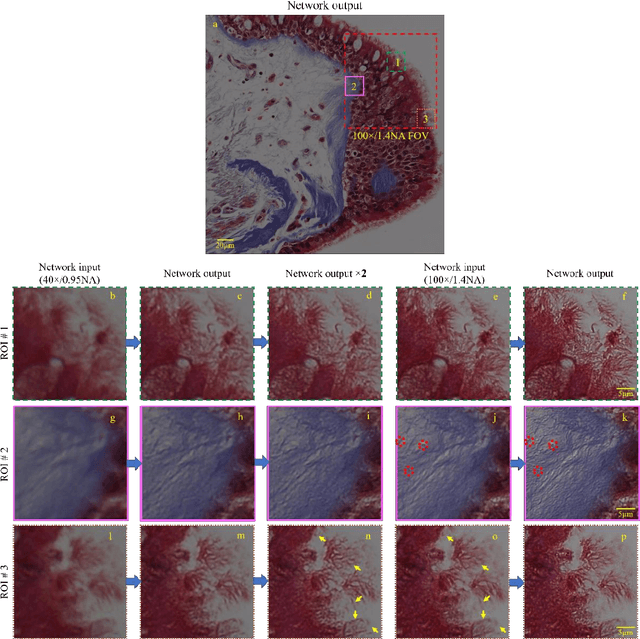

Abstract:We demonstrate that a deep neural network can significantly improve optical microscopy, enhancing its spatial resolution over a large field-of-view and depth-of-field. After its training, the only input to this network is an image acquired using a regular optical microscope, without any changes to its design. We blindly tested this deep learning approach using various tissue samples that are imaged with low-resolution and wide-field systems, where the network rapidly outputs an image with remarkably better resolution, matching the performance of higher numerical aperture lenses, also significantly surpassing their limited field-of-view and depth-of-field. These results are transformative for various fields that use microscopy tools, including e.g., life sciences, where optical microscopy is considered as one of the most widely used and deployed techniques. Beyond such applications, our presented approach is broadly applicable to other imaging modalities, also spanning different parts of the electromagnetic spectrum, and can be used to design computational imagers that get better and better as they continue to image specimen and establish new transformations among different modes of imaging.